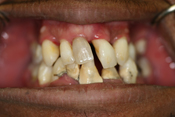

WORST TEETH Pictures from Warren Dentistry

This can happen to your teeth when proper Dental Hygiene is not practiced.

Patient 1